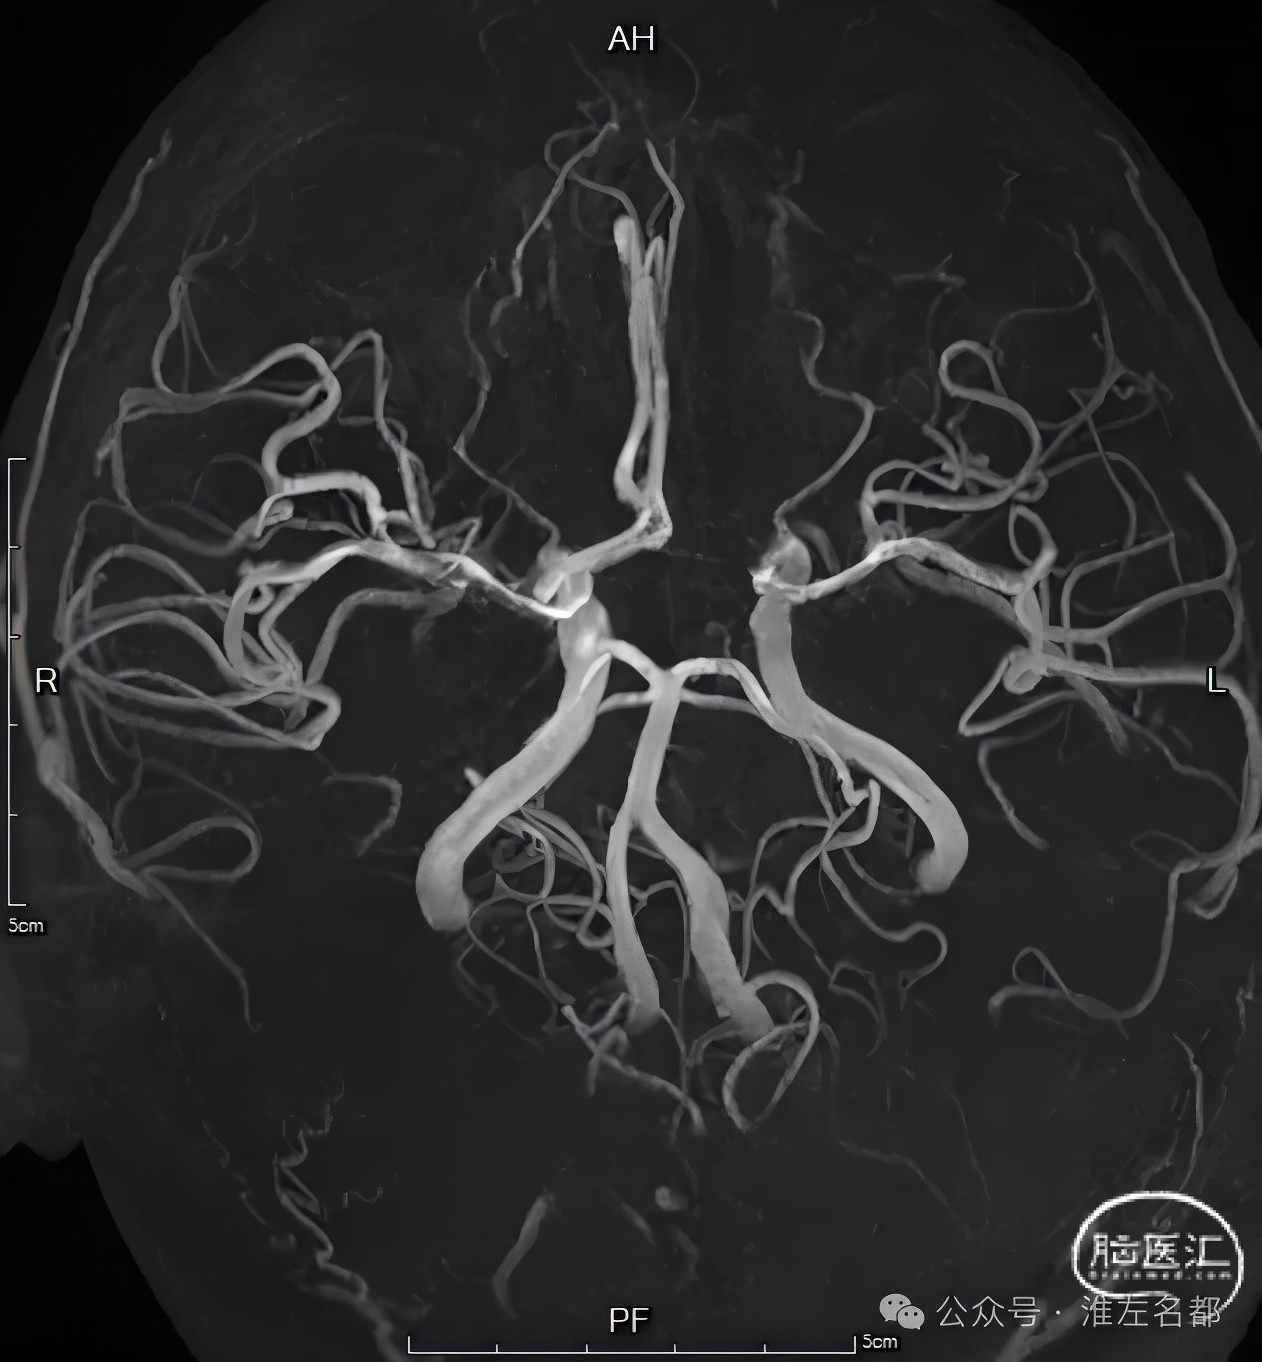

颅脑CTA:右侧颈内动脉分叉部闭塞,累及MCA和ACA近端,颈内动脉分叉部可见血管高密度影。

CTP:右侧半球和左侧大脑前动脉区大范围严重低灌注区,核心梗死主要位于额叶,可见大范围“组织窗”。

颅脑3D-TOF-MRA:右侧大脑中动脉和双侧大脑前动脉显影通畅。